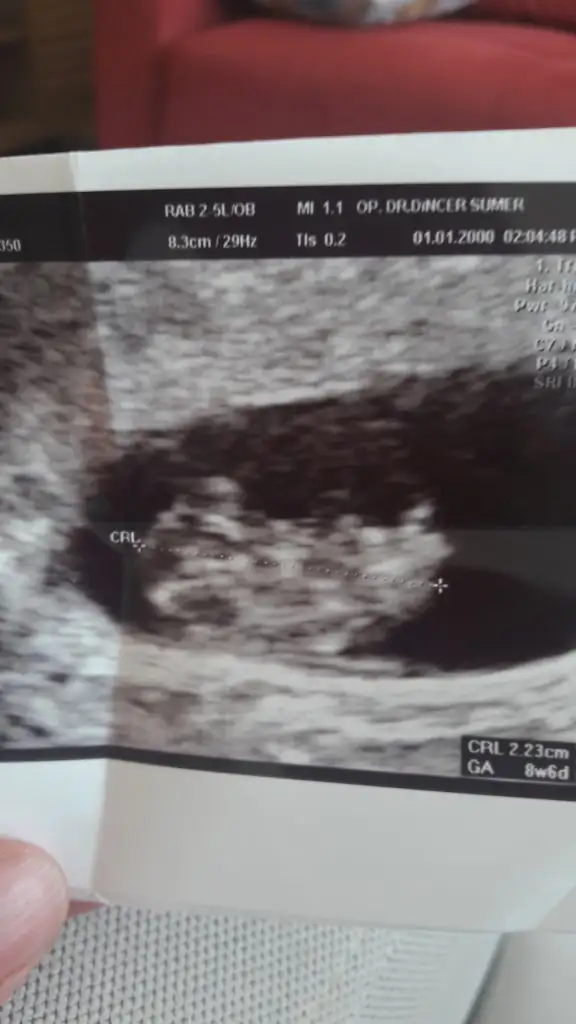

Kızlar yorumlayacak var mı? Karından ultrason. 7 haftalık.

6 yada 7 haftalık olmalı buna göre erkek ama nub teorisi biraz daha netlik varArkadaşlar buna da yorum yapabilir misiniz

Biraz saga yakın kız gibi 11 yada 12 hafta nub haftası paylaşırsanız tahmin ederizMerhaba arkadaşlar. Konuya hakim olanlar bana da yardimci olabilir mi? Karından ultrason. Plesentayı anlayamiyorum ben

Tesekkurler. Plesentayı ayırt edebiliyor musunuz? Kesenin cevresinin tamamı parlak ve beyaz. Bariz bir goruntu anlayamiyorum da benBiraz saga yakın kız gibi 11 yada 12 hafta nub haftası paylaşırsanız tahmin ederiz

Bebegin oldugu yer plesenta ama 11 yada 12 hafta usg de paylaşırsınız nub teorisi dogru oluyot nubuda belliyseTesekkurler. Plesentayı ayırt edebiliyor musunuz? Kesenin cevresinin tamamı parlak ve beyaz. Bariz bir goruntu anlayamiyorum da ben